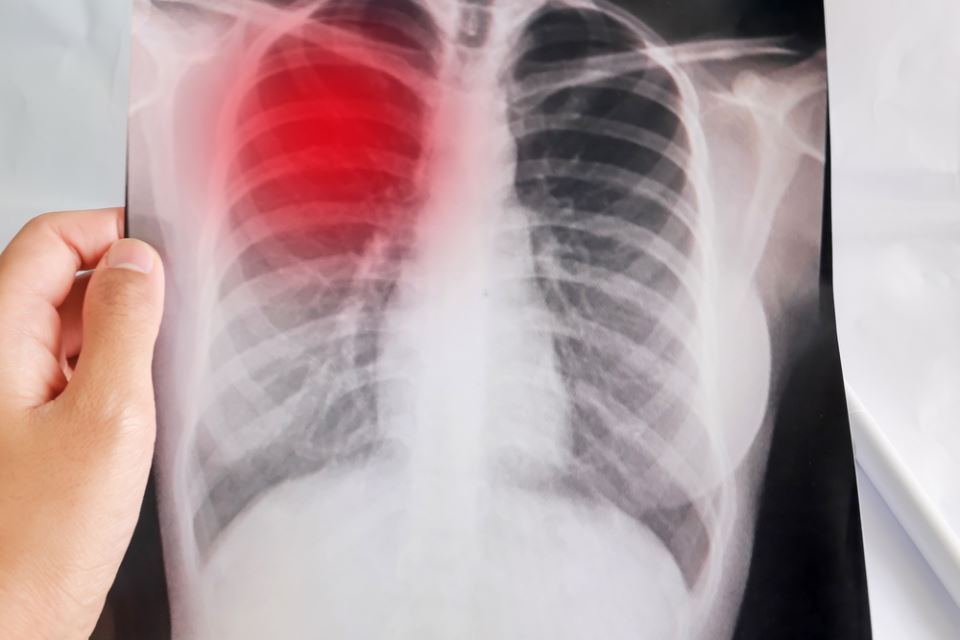

Големата кашлица (пертусис) може да ја добие секое дете, а особено се изложени на ризик новороденчињата и децата до петгодишна возраст. Може да се појави и кај возрасни, кои сепак полесно ја прележуваат.

Големата кашлица е вид респираторна инфекција која во најголем број случаи ја предизвикува бактеријата "Bordetella pertussis". Постојат повеќе фактори или предизвикувачи кои можат да доведат до нејзина појава, меѓу кои се:

Дополнителни симптоми се недостаток или прекини на доток на воздух во белите дробови (апнеа), како и сина боја на кожата (цијаноза).